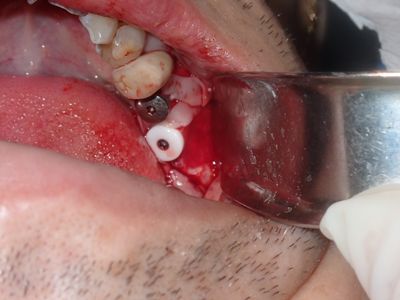

relatively straight forward implant placement, some bone expansion and countersinking. buccal bone thin, grafted with sticky bone from allograft folloewd by collagen mmebrane soaked in prf fluid, additional fibrin membrane used